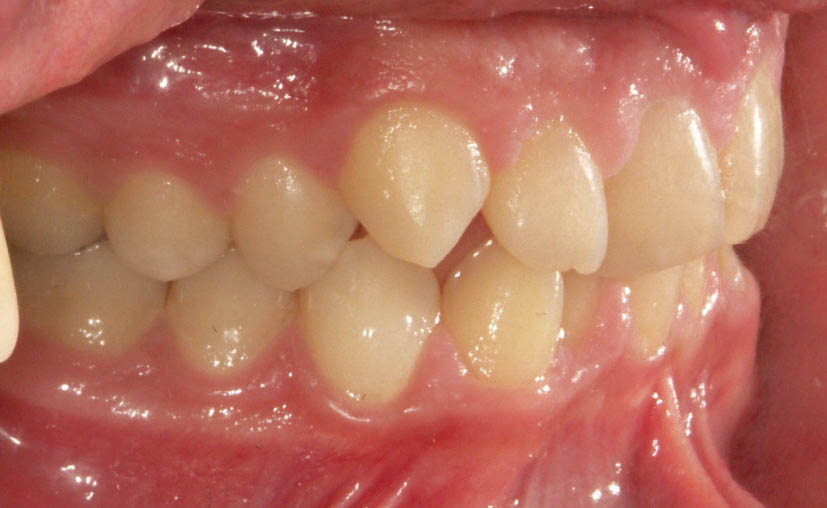

شکل 103-2: اکلوژن کلاسI در سمت راست